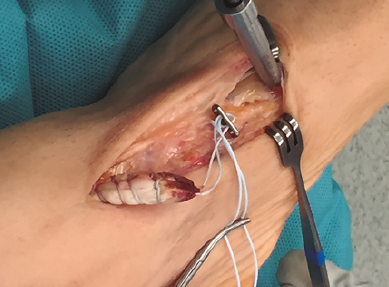

Figura 5. Inserción de la placa metálica a través del túnel óseo.

Se realiza túnel con broca de 4,5 mm al nivel de la cortical dorsal de la cuña medial con oblicuidad de proximal a distal hasta llegar a la cortical plantar (Figura 4). Posteriormente, se ensancha el mismo al nivel de la primera cortical según el diámetro del tendón tibial anterior, utilizando una pinza gubia o un avellanador.

Figura 6. Tracción de los hilos para deslizar el tendón tibial anterior en el túnel óseo.

Se procede a la introducción de la placa al nivel del túnel transóseo hasta empujarla fuera de la cortical plantar (Figura 5). Posteriormente, se introduce el tendón en el túnel de la cuña mediante la tracción de los hilos (Figura 6). En este paso resulta útil en ocasiones embocar con ayuda de un mosquito el tendón a la entrada del túnel óseo.

Figura 7. Anudado con ayuda de un empujahilos.

Finalmente, se realiza el anudado de la sutura sobre el sistema de fijación con ayuda de un empujanudos (Figura 7).